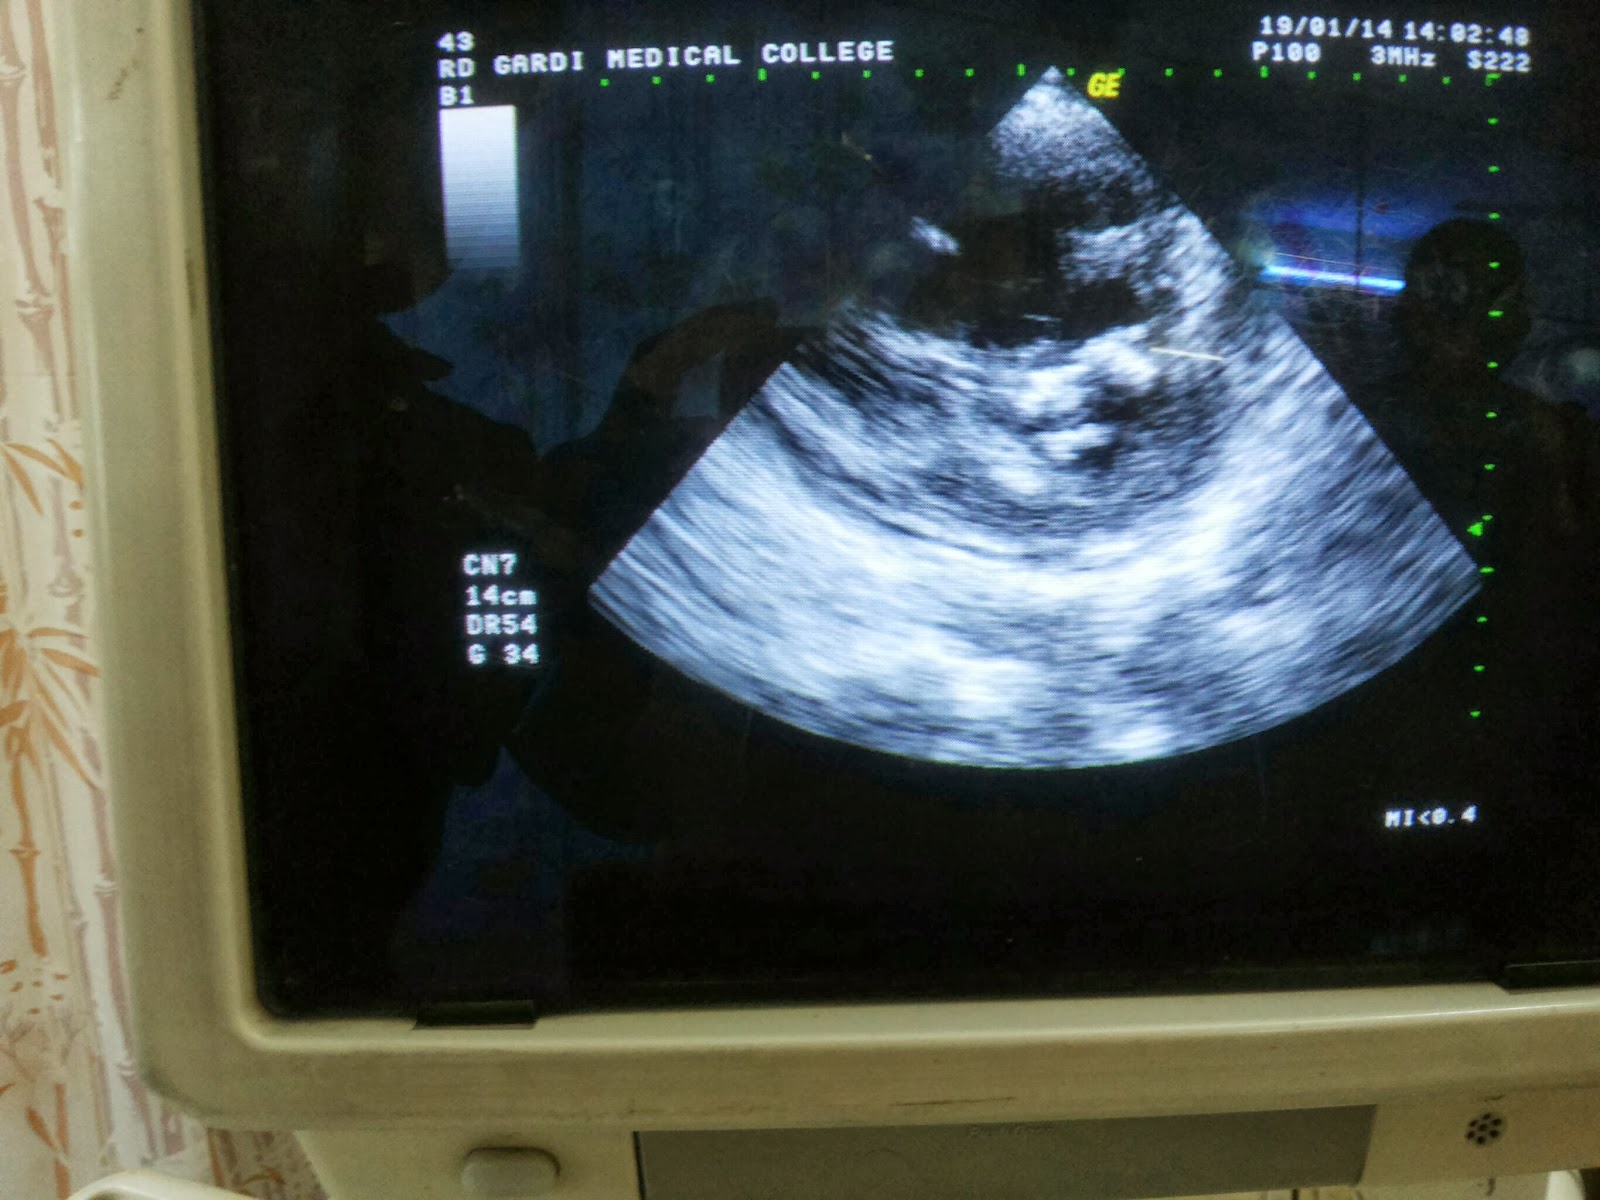

An Interesting case of TRUCUSPID VALVE TEAR in a patient with RHD

Patient was. 30/M, known RHD, presented with

Acute onset SOB GR IV NYHA

chest pain

Palpitations.

On clinical examination,

Pulse 120bpm regular rhythm (sinus tachycardia)

BP 90/60 mm Hg

JVP FULL

B/L minimal pitting pedal edema

CVS

apex L 5th ICS inside MCL tapping type

PALPABLE THRILL AT MITRAL AREA

DIASTOLIC SHOCK (palpable P2) at PA

Palpable thrill at tricuspid area

LOUD P2 at Pulmonary area,

SOFT S1 at Mitral area

MDM GR IV at MA ,low pitched,rumbling murmur, best heard with bell in Left lateral position at expiration.

PSM GR IV at TA ,high pitched , best heard in supine position at end expiration

EDM at NAA Gr II high pitched, best heard I'm sitting position at end expiration.

ECG FINDINGS

Bi Atrial enlargement…

RV +

ECHOCARDIOGRAPHY FINDINGS

Heavily calcified Mitral Valve leaflets

Severe MS

MVA 0.66 cm ²( PHT method)

0.82cm ² ( PSAX Planimetry)

Grossly dilated RA &RV

RA volume approx 300 -350,ml

(77x70x71)

RVID basal Diameter 41mm

And now the most interesting finding

Severe TR WITH  'Double ' JET

I tried to see if the jets were arising fromthe same place, but on close observation  and different planes & views, it was clear that both jets were different.

One jet arised from the normal TRICUSPID INFLOW while the other jet originated somewhere laterally .

The velocities of both these regurgitant jets were different.

Central jet being 4.5 m/s

While lateral jet 2.6m/s

They both gave a separate distinct jets visible on Color Doppler.

there was also mild PULMONARY REGURGITATION,

Mild MITRAL REGURGITATION

MILD AORTIC STENOSIS WITH MILD AORTIC INCOMPETENCE.

thankfully there were no clots.

FINAL DIAGNOSIS :

VHD

severe MS (?CRITICAL) with heavily calcified both leaflets

mild MR

Grossly dilated RA RV

SEV TR WITH DOUBLE JET (? TRICUSPID LEAFLET PERFORATION)

SEV PAH

(PASP 75 mm Hg)

Mild AS with AR.

Probably Rheumatic in origin

An interesting case of ?RV CYST ?Pulmonary Embolism

Patient is a 48yr old female , who presented to us with c/o SOB GRIII /IV NYHA

cough

Low grade fever

swelling all over body

since 8 days

She was treated at various hospitals for her condition diagnosed from LRTI to pericardial effusion.

Clinically she had tachycardia, BP was 100/70

Pitting pedal edema

Full JVP

APEX L 5TH ICS INSIDE MCL

PROMINENT EPIGASTRIC N SUPRASTERNAL PULSATIONS

PALPABLE P2

Loud P2

PSM GR III at TA

RS

trachea central

B/L crepts IMA ISA L>R

ECG findings :

P pulmonale in lead II(RAE)

right Axis deviation

R positivity in V1 V2

(RVH)

incomplete RBBB

I performed a bedside ECHOCARDIOGRAPHY

WITH FOLLOWING FINDINGS

DILATED RA RV

RVID 38mm

Severe TR

TR Vmax 3.6 m/s

Tr Max PG 56 mm Hg

Mild PR

CLOT in RA Appendage

And CLOT IN RV APEX (15-20cc each)

DILATED IVC (18.5mm)

Since ECHO was bedside it remains to be checked if there was an ASD or not.(on a better machine maybe)

patient was started on Anticoagulants immediately with target INR 2.5-3.5.

Pulmonary embolism is often missed out on routine diagnosis.

The triad of Cough ,Shortness of breath , Hypotension must be kept in mind for every patient with unexplained symptoms.

This patient had cardio megaly on x ray

And poor R progression inECG

She was misdiagnosed as CAD n LRTI

In this case patient presented when she developed CCF secondary to Right sided failure.

So moral of the story : Always think of PULMONARY EMBOLISM whenever any pt presents with unexplained cough DYSPNEA .

Corelation of CLINICAL FINDINGS, ECG AND ECHO ARE A MUST.

Images attached.

Comments n queries most welcome..

Update : 22/01/2014

Cardiologist opinion is that its a RV Cyst n not a clot.

Were searching for cysts in other areas